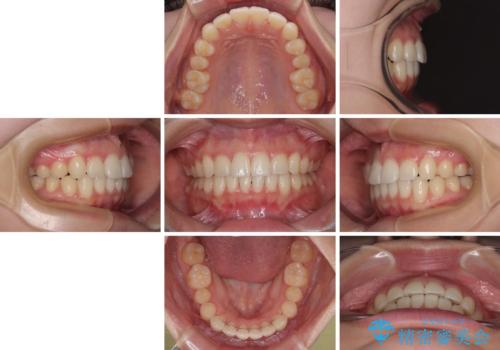

- 上下前歯のデコボコを気にして来院された患者様です。

ワイヤー矯正でもマウスピース矯正でも可能でしたが、短期間で、自身の手を煩わせることなく治療を行いたいとのことで、ワイヤー装置にて矯正治療を行うこととしました。

舌の突出癖により、出っ歯仕上がりとなる可能性がありましたが、舌のトレーニングを頑張っていただき、1年強で終えることができました。